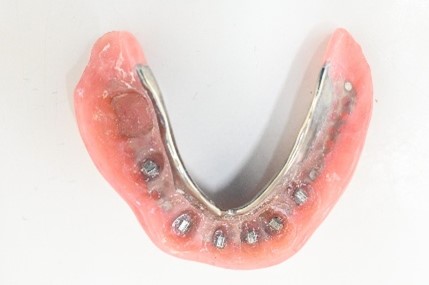

【マグネット式総入れ歯】

青丸は組み込まれたマグネット

上顎

下顎